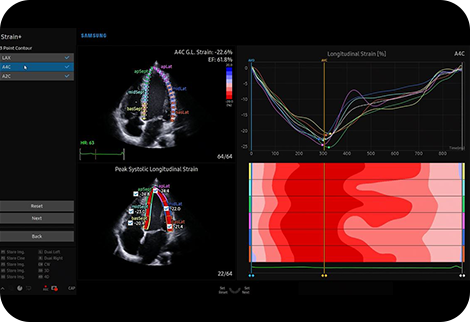

Quantify wall motion

of the left ventricle

Strain+ ¹ is a quantitative tool for measuring global and segmental wall motion of the left ventricle (LV). Three standard LV views and a Bull’s Eye are displayed in a quad screen for easy assessment of the LV function.